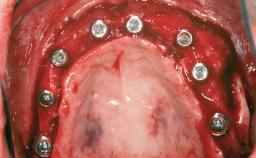

# of Implants 14

Bone Augmentation Horizontal|Sinus Floor Elevation|Staged|Vertical

Defining Characteristics Fully edentulous upper jaw to be rehabilitated with four or more implants

Modality Fixed hybrid bridge on 5+ implants